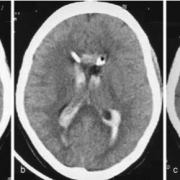

Materials and Methods The average cerebrospinal fluid (CSF) drainage volumes were

analyzed. Computed tomography (CT) scans were performed on admission, 24 hours

and 48 hours after EVD placement, and then on days 5 and 8. Patient group 1 was

treated with a single EVD; patient group 2 was treated with bilateral EVDs. The IVH

volume was calculated in all ventricles. A multivariate analysis was conducted to

Results The percentage of IVH volume change was found to be significantly higher in

the dual-catheter group compared with the single-catheter group (p 1⁄4 0.0034) after

5 days of EVD. The mean reduction in IVH volume was 17.36 (mL) in patients 45 years

of age and 20.50 (mL) in patients > 45 years. The multivariate analysis suggested the

following significant predictors for IVH volume reduction: age of the patient

(p 1⁄4 0.011) and longer duration (days) of EVD (p 1⁄4 0.028). The age of the patient

had a weak positive association and duration of EVD had a positive association with the

IVH volume reduction.